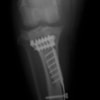

Fixin T字プレート使用して固定

・術後レントゲン

手術前TPA 28.4° が術後TPA 11.7° に矯正されました。

術前TPA計測

手術前

術後TPA計測

手術後

当院ではFixinmicroプレートを使用して小型犬のTPLO手術を実施しております。